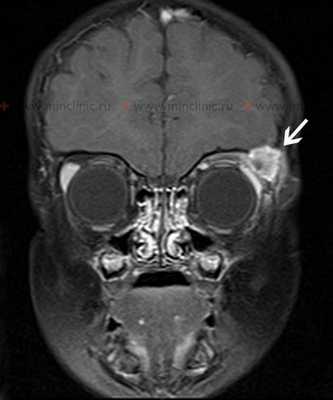

МРТ головного мозга и костей черепа с контрастирование - T1 взвешенное изображение на коронарном срезе демонстрирует эозинофильную гранулему как массу, накапливающую контраст, в области левой орбиты на уровне верхней части височной кости.